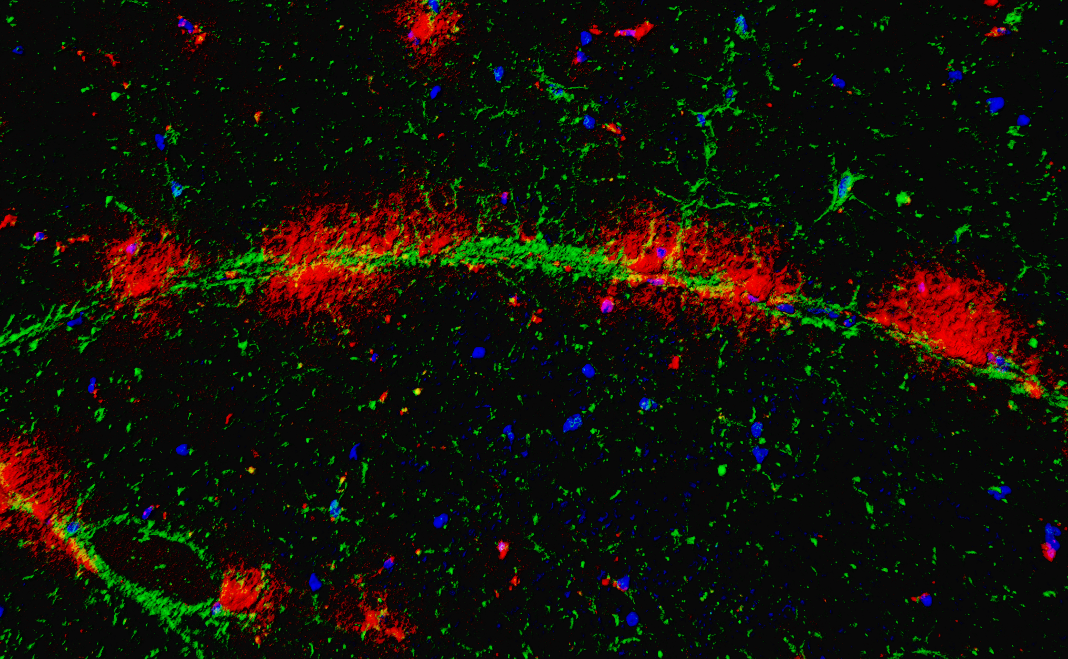

为进一步揭示运动神经元老化的原因,研究人员绘制了一张详细的食蟹猴衰老脊髓单细胞转录组导航图。按图索骥,研究人员寻找到驱动运动神经元衰老的罪魁祸首,即一群在老年灵长类脊髓中特异性积累的CHIT1高表达的激活型小胶质细胞(AIMoN-CPM)。通过组织病理学、细胞生物学和分子生物学分析,研究人员发现AIMoN-CPM倾向于聚集在衰老的运动神经元周围,并通过旁分泌CHIT1蛋白激活周边运动神经元中的SMAD信号,进而驱动后者的衰老和退行。

图2.衰老灵长类脊髓中AIMoN-CPM小胶质细胞(红色)在运动神经元轴突(绿色)处聚集